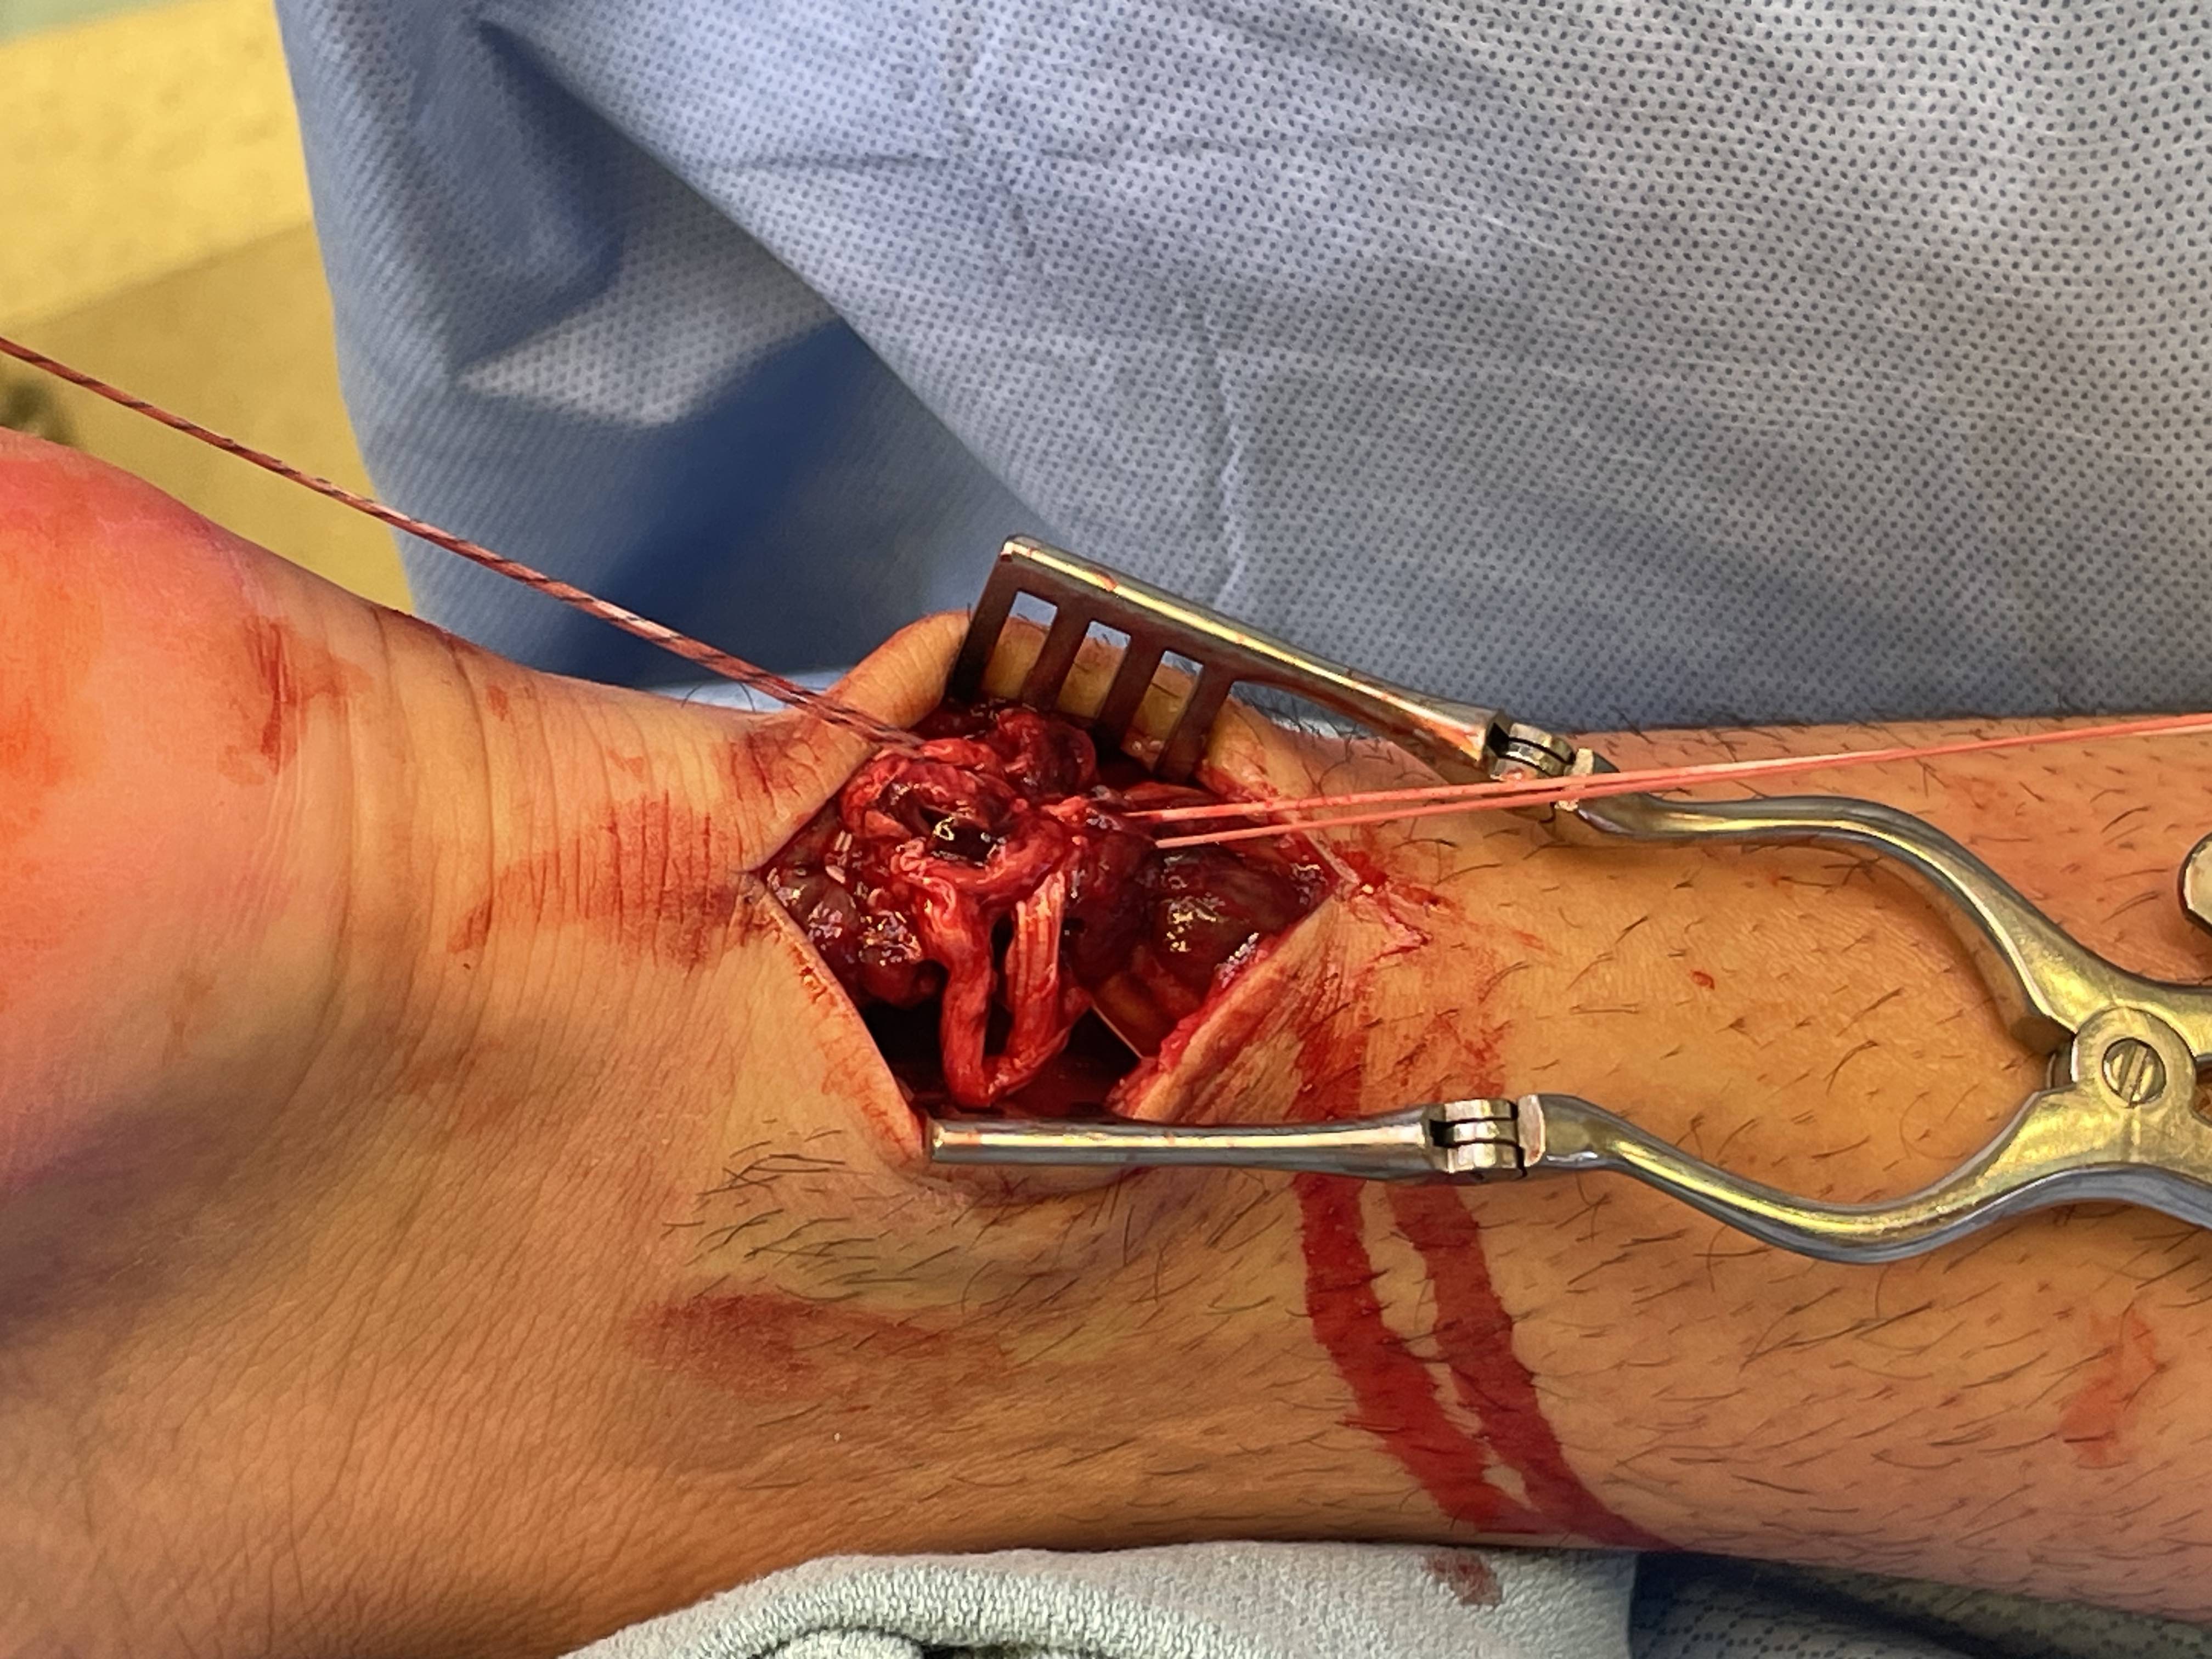

Open tendoachilles repair

Technique

Vumedi open achilles tendon repair

Prone position with tourniquet

- slightly medial incision to protect sural nerve

- full thickness skin flaps to paratenon

- identify and protect sural nerve

- divide paratenon longitudinally

- can incise paratenon in the midline anteriorly which increases tissue available for closure

- Bunnell Suture / Krackow suture x 2 with high strength suture / fibre wire

- one in proximal and one in distal tendon ends

- tie via two knots with foot fully plantar flexed

- +/- augment with circumferential 4.0 suture to minimize bunching

- careful closure of paratenon to prevent skin adhesions

- front slab in plantarflexion 2 weeks

- then standard accelerated rehabilitation

Anterior release of paratenon to allow posterior closure over achilles repair

Repair with proximal and distal Krackow high strength sutures